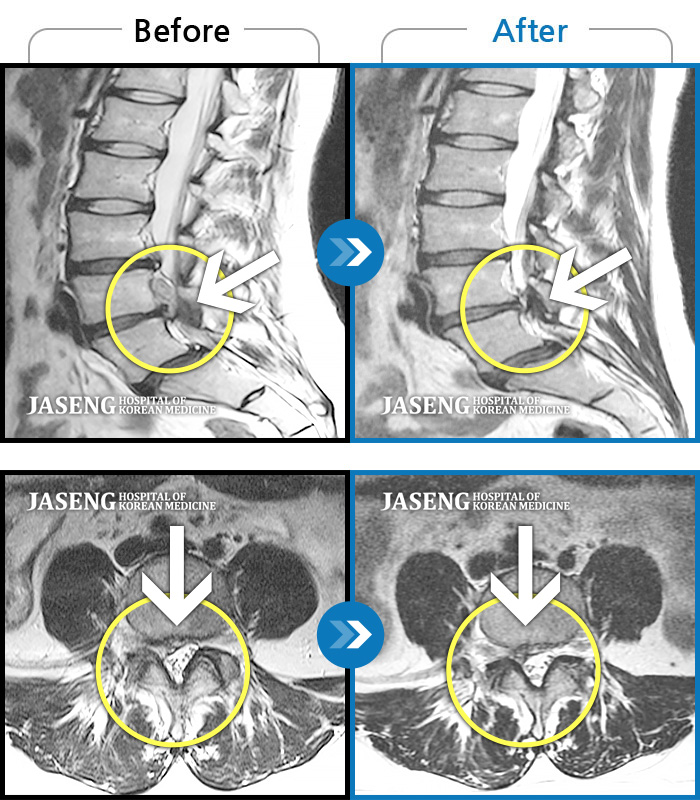

MRI 치료사례

허리 골반통증 및 우하지 방사통, 감각저하